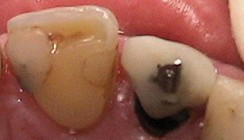

Am Tag des Unfalls wurde die Wurzeloberfläche des avulsierten Zahnes zunächst mit NaCl abgespült (Abb. 2). Die knöchern völlig intakte Alveole wurde ebenfalls mit NaCl gespült. Dabei ist darauf zu achten, dass das in der Alveole entstandene Koagulum vorsichtig und vollständig ausgespült wird, ohne dass die parodontalen ­Fasern und Zementoblasten verletzt werden (Abb. 3). Anschließend wurde der avulsierte Zahn 21 mittels einer Frontzahnzange in seine Alveole replantiert und mit ­einer Draht-Kunststoff-Schiene geschient (Abb. 4). Am vitalen frakturierten Zahn 11 wurden die pulpanahen Bereiche mit einem Kalziumhydroxidpräparat abgedeckt und dieses provisorisch mit einem Flow fixiert. Anschließend wurde eine Röntgenaufnahme zur Kontrolle der Replantation angefertigt (Abb. 5). Es wurde ein Rezept über ein Analgetikum sowie ein Antibiotikum ausgestellt. Für den folgenden Tag wurde ein Kontrolltermin in der Oralchirurgie sowie der erste Termin in der Zahnarztpraxis für Kinder bei Dr. Christina Masuck vereinbart.

Die Aufbereitung erfolgte maschinell mit Pro Taper Universal sowie mit Handinstrumenten aufgrund des recht großen Kanallumens. Zunächst wurde der Zahn nach Spülung mit NaOCl (5%) und EDTA (17%) mit einer Kal­ziumhydroxid-Einlage versorgt und provisorisch verschlossen. Im darauffolgenden Termin wurde zunächst die Draht-Kunststoff-Schiene entfernt. Alle Zähne er­wiesen sich als fest (Abb. 8). Nach Anlegen des Kofferdams und abschließender Säuberung und Spülung mit NaOCl (5%) und EDTA (17%) wurde der vollständig aufbereitete Kanal getrocknet und anschließend mit Guttapercha und AH Plus bis zum Apex abgefüllt (Abb. 9 und 10). Somit war die endodontische Behandlung an Zahn 21 abgeschlossen.